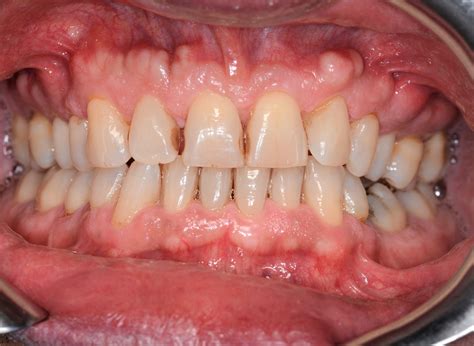

Bony growths on gums are typically benign and can be categorized into different types based on their location and appearance. The most common types include:

• Torus Palatinus: This is a bony growth that occurs on the roof of the mouth.

• Torus Mandibularis: This type of growth is found on the lower jaw, near the premolar teeth.

• Exostosis: These are bony projections that can occur on the jawbone, often near the molars.

These growths are usually painless and do not cause discomfort unless they become large enough to interfere with normal oral functions.

Bony growths on gums are often asymptomatic, meaning they do not cause any noticeable symptoms. However, in some cases, individuals may experience:

• Discomfort or pain, especially if the growth is large or interferes with normal oral functions.

• Difficulty chewing or speaking, particularly if the growth is located on the roof of the mouth or near the teeth.

• Visible lumps or bumps on the gums or inside the mouth.